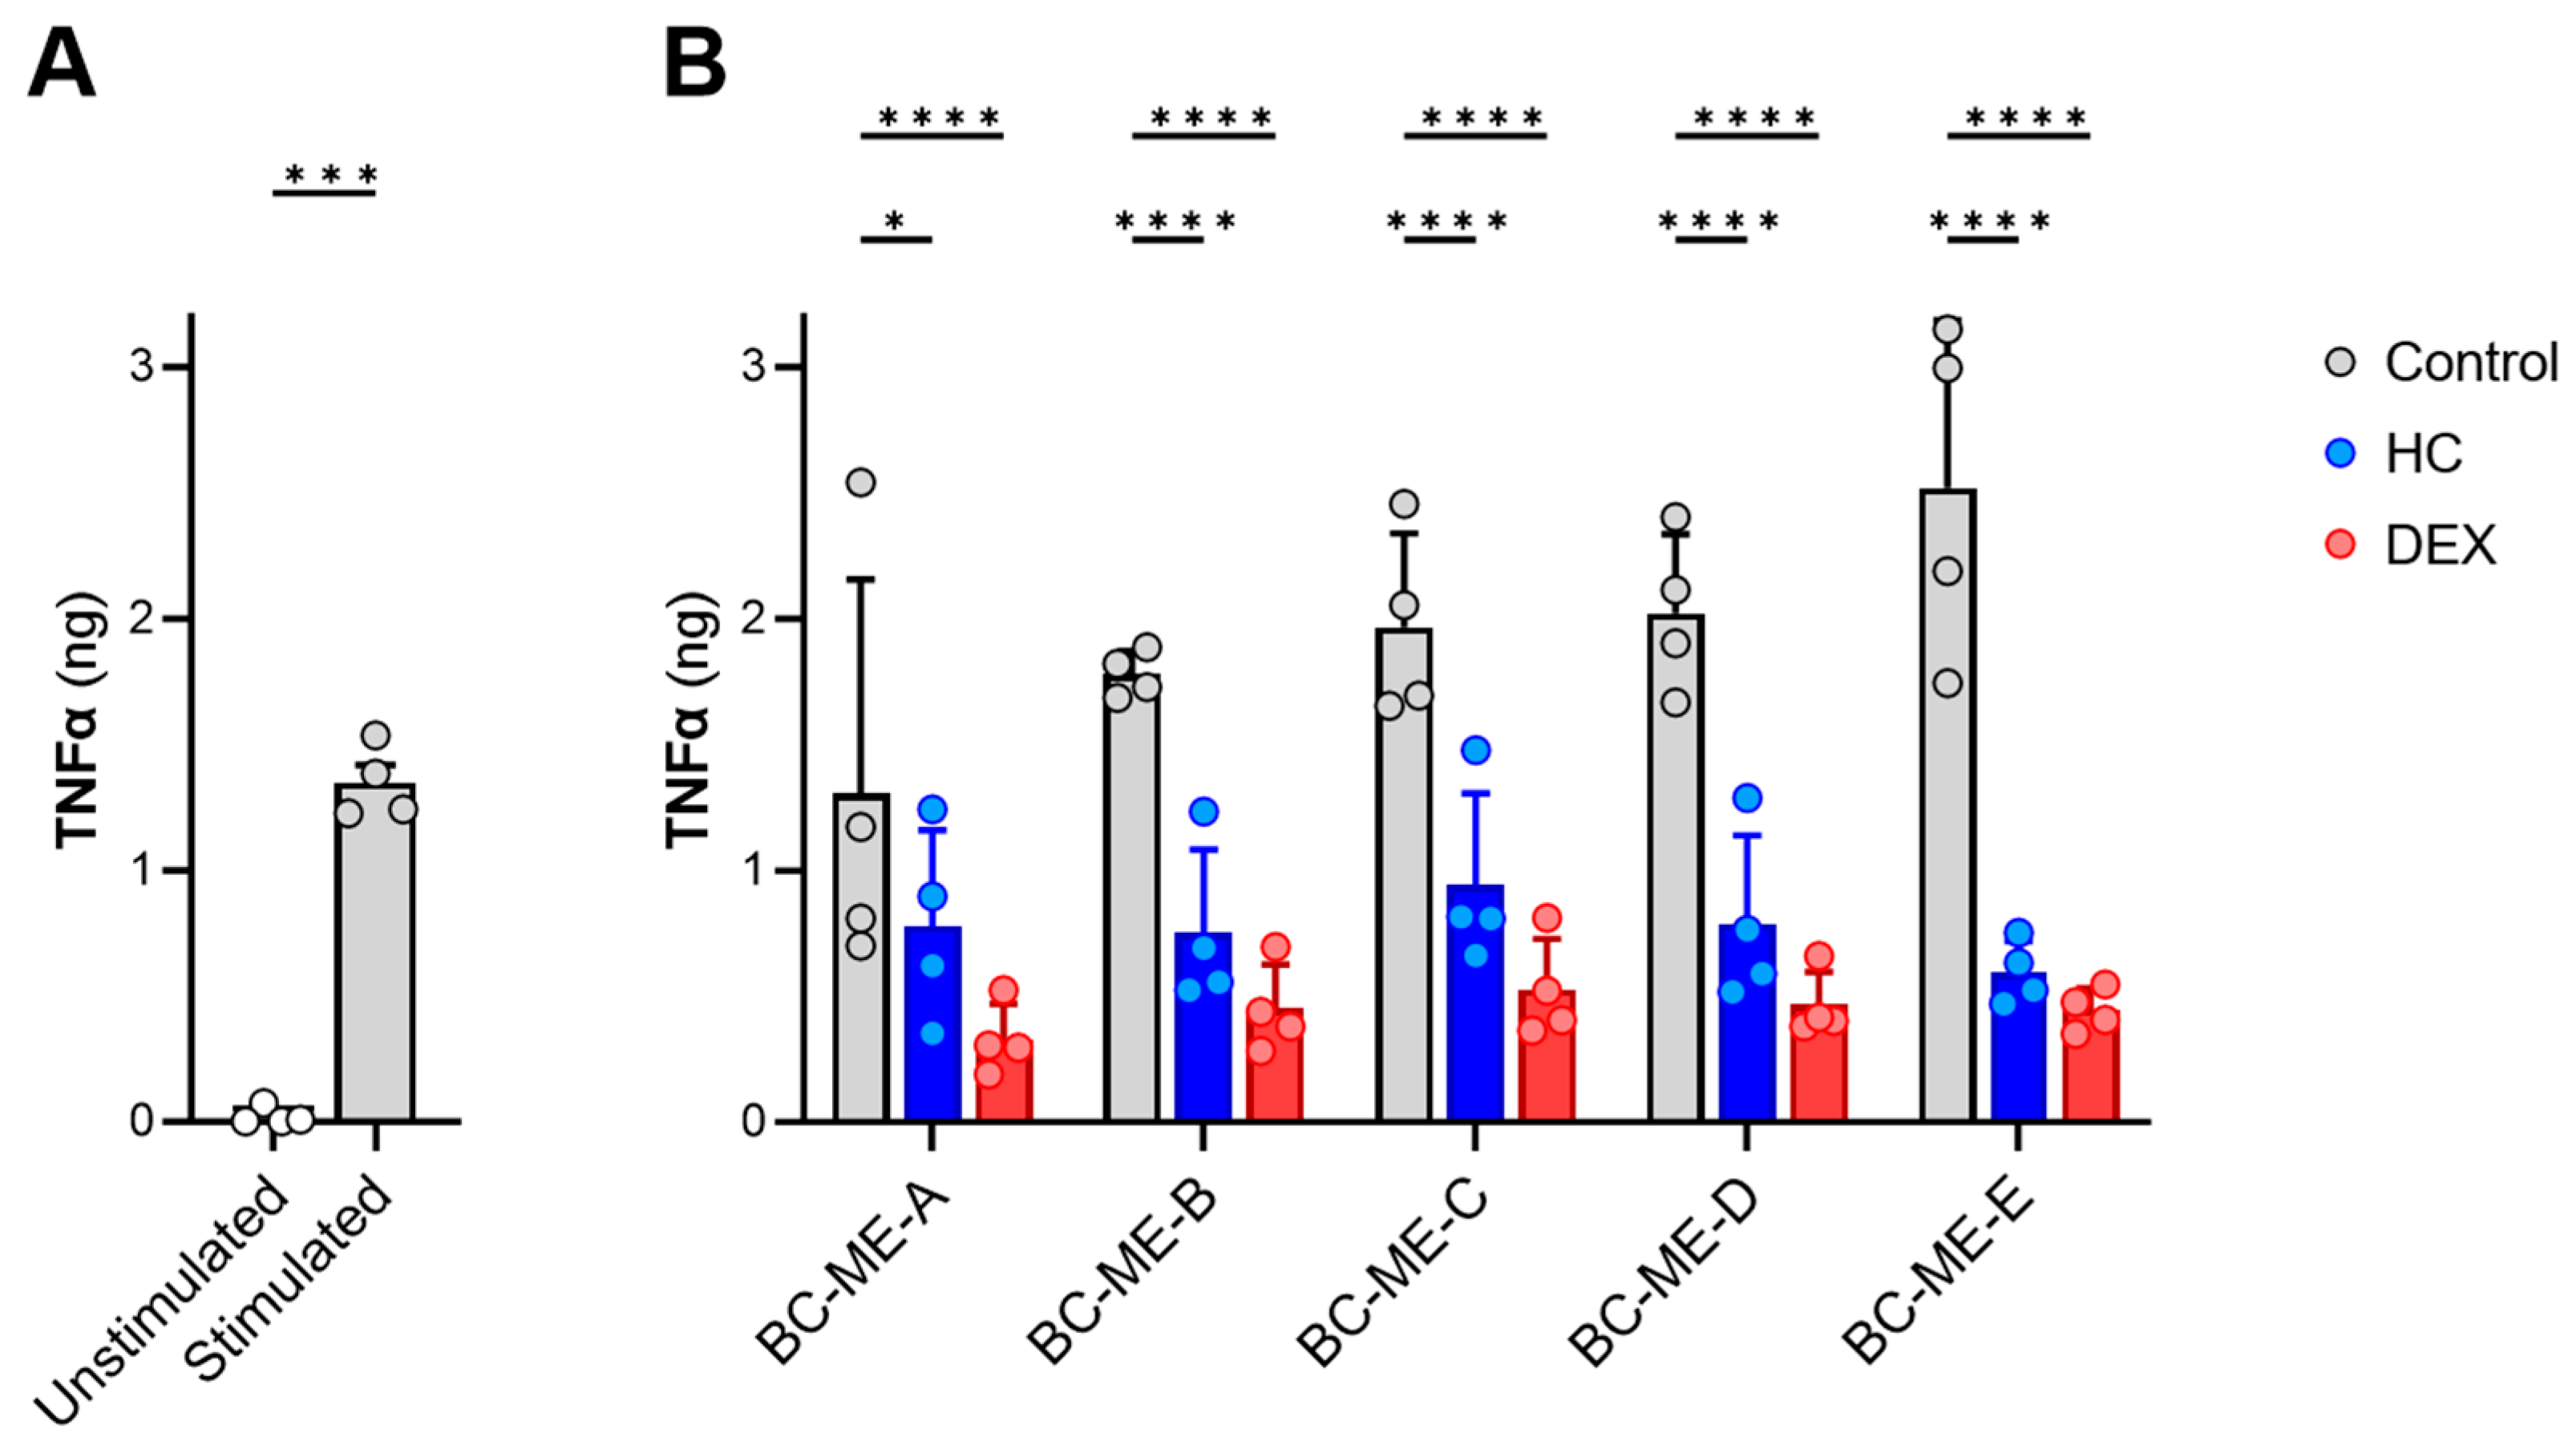

3.3.5. Anti-Inflammatory Activity